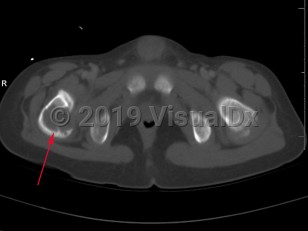

Eosinophilic granuloma of bone in Adult

Langerhans cell histiocytosis (LCH) refers to a spectrum of diseases that includes eosinophilic granuloma (EG), Hand-Schuller-Christian disease, and Letterer-Siwe disease. EG is a rare (seen in 1-5 per million), benign tumor-like disorder that features clonal proliferation of Langerhans cells (antigen-presenting mononuclear cells of dendritic origin) usually found in bones; however, this can involve other organ systems. EG occurs most often in children aged 5-15 years, with a male-to-female ratio of 2:1. EG constitutes 60%-80% of cases of LCH and accounts for less than 1% of all bone tumors. Ninety percent of cases involve a single lesion, usually in the axial skeleton, with just under 10% of cases involving lesions in multiple bones or lesions in other organ systems (ie, skin, pituitary gland, gastrointestinal [GI] tract, lung, spleen, or brain).

The clinical presentation of EG depends largely on the location affected. EG is most often confined to the axial skeleton. EGs are often asymptomatic and found incidentally, or may initially present with pain and swelling of the affected area, with or without decreased range of motion. Commonly affected areas of the skeleton include (in order of frequency): skull, femur, pelvis, mandible, clavicle, ribs, and long bones (of the diaphysis and metaphysis).

Within the spine, EG accounts for 6.5%-25% of all spinal tumors, with the most common location being the thoracic spine, followed by the lumbar and then cervical spine. In cases of EG of the spine, the following symptoms have been reported: neck / back pain, limb weakness, neck / back stiffness with restriction of movements, kyphotic deformity, radiculopathy, and torticollis.